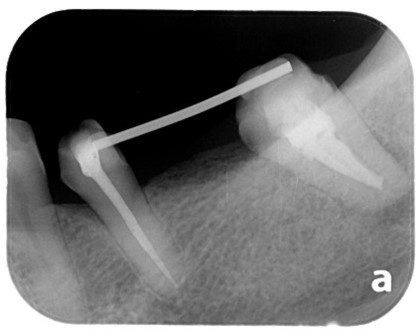

案例:蓄意再植

原先病人做牙橋的大臼齒因為牙根發炎,疼痛難耐,前來做根管治療,但因為大臼齒牙根末端神經較複雜、且有張口困難的問題,因此更增加了做根管治療的困難度,在經醫師評估後,建議做蓄意再植手術。

將牙齒拔出後,在口外做根管治療、並且切除牙根末端神經較複雜處。

醫師在口外對牙齒完成治療後,再將牙齒植入同一位置

治療前:蛀牙嚴重、牙根發炎。

治療前X光片。

治療中:牙齒在口外治療完種回去,並用鐵線固定,等待傷口復原.

治療中:將牙齒修型、將鐵線拆除